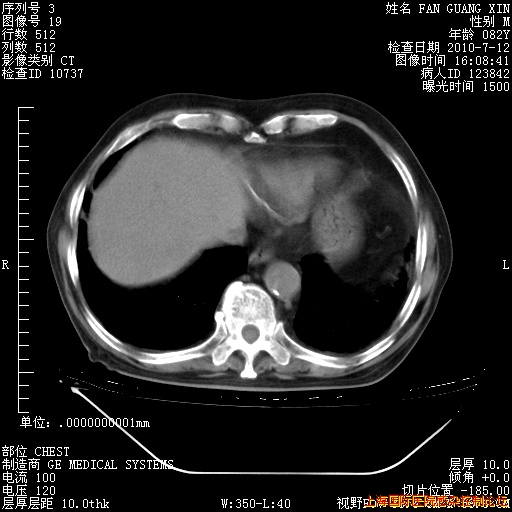

今天复查CT

今天CT

整整相隔30天的肺部CT好像有所好转啊。甲强龙减量第3天,需要观察体温。

海管,自昨日你和我通完话后,不知您岳父消化道症状有无缓解?体温怎样?阅读7.12日胸部ct,个人认为目前激素治疗是有效的,甲强龙减量是适宜的。因在抗痨治疗,需密切观察肝功、肾功能和血常规。不过,老年、长期住院和大量使用激素,很担心菌群失调发生